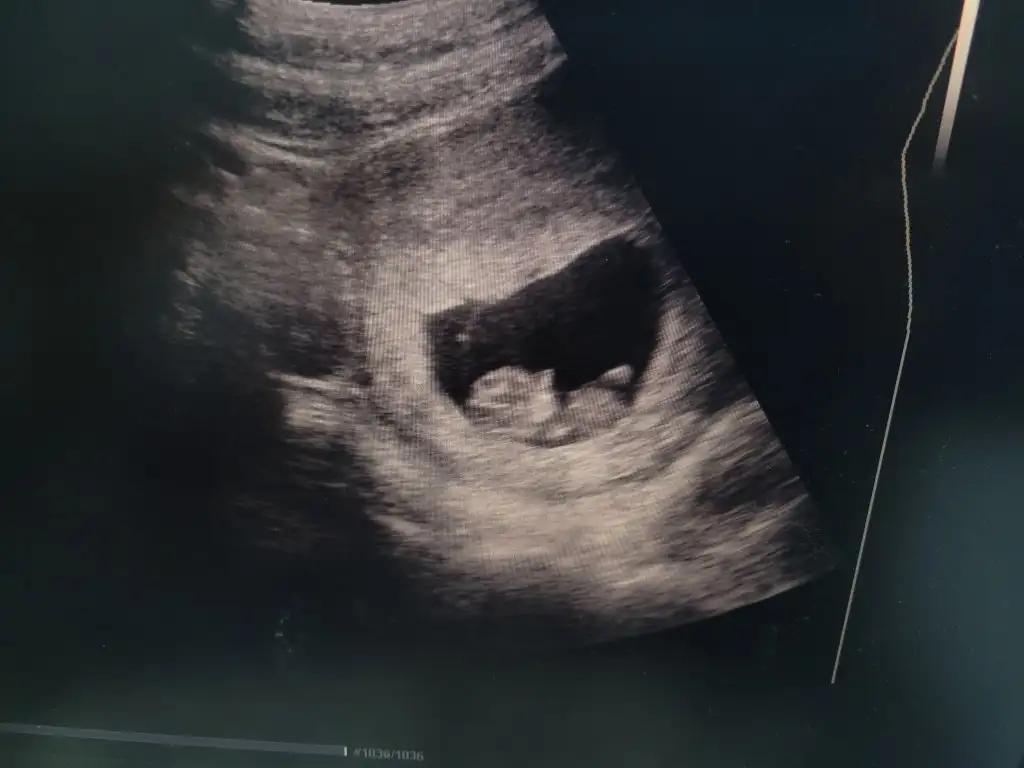

E hadi madem Papatyamaviss Papatyamaviss bana da bi tahmin yap kusur kalmayayım kızlar isteyen yorumlasın ben tahminimi söylemiycem ☺️

Eklentiler

• 1455DF28-EC45-4CC6-B74E-10578F9A4186.webp

1455DF28-EC45-4CC6-B74E-10578F9A4186.webp

50,1 KB · Görüntüleme: 61